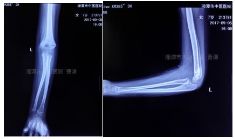

外院片如下:

杨氏四步复位法整复后拍片复查

治疗两月余拍片复查